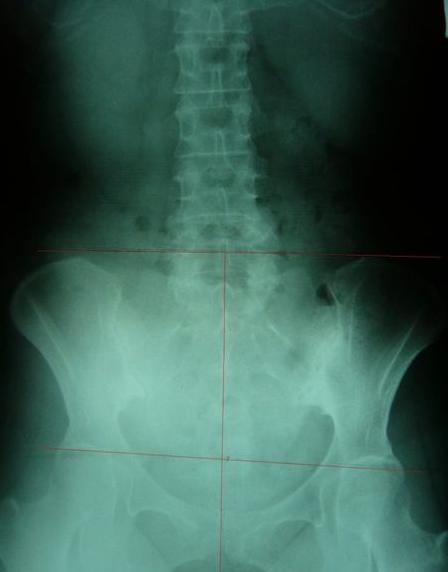

一般最常见到骨盆歪斜的案例包括产后骨盆不正、车祸、撞击、跌倒、姿势不良…等等造成。骨盆歪斜的典型症状包括腰部、髋臀部、腿、膝部疼痛。列举三个自在美国取得脊医执照以来曾经处理过骨盆歪斜相当明显的案例。都是骨盆部位曾经遭受撞击。案例A是超过十年以上的陈年车祸旧伤、另一案例B是急性摔伤(两天内)的案例。两者的X光片都依照美国脊医X摄影方式采站姿摄影评价。借此同时评价骨盆在重力(gravity)影响下的反应。也可以泯除躺歪斜摄影而造成图像不正的情况。最简单的评价要点包括骨盆高低边?中线是否穿越耻骨联合?左右两边是否对称?我简单的几条线一画,相信连外行人也可以看出明显的骨盆歪斜的情况。案例A属陈旧性伤害在调理约两个月后明显降低腰臀腿部的不舒服。而案例B属急性伤害,案例B在调理近三周后骨盆疼痛由原先的持续疼痛降低为完全不痛。之后的骨盆X光摄影重新评价也显示骨盆旋转的问题大幅改善。

案例B:左图调理前骨盆严重歪斜左右极不对称 ;右图调理后骨盆歪斜改善骨盆圈呈现对称心型圆弧